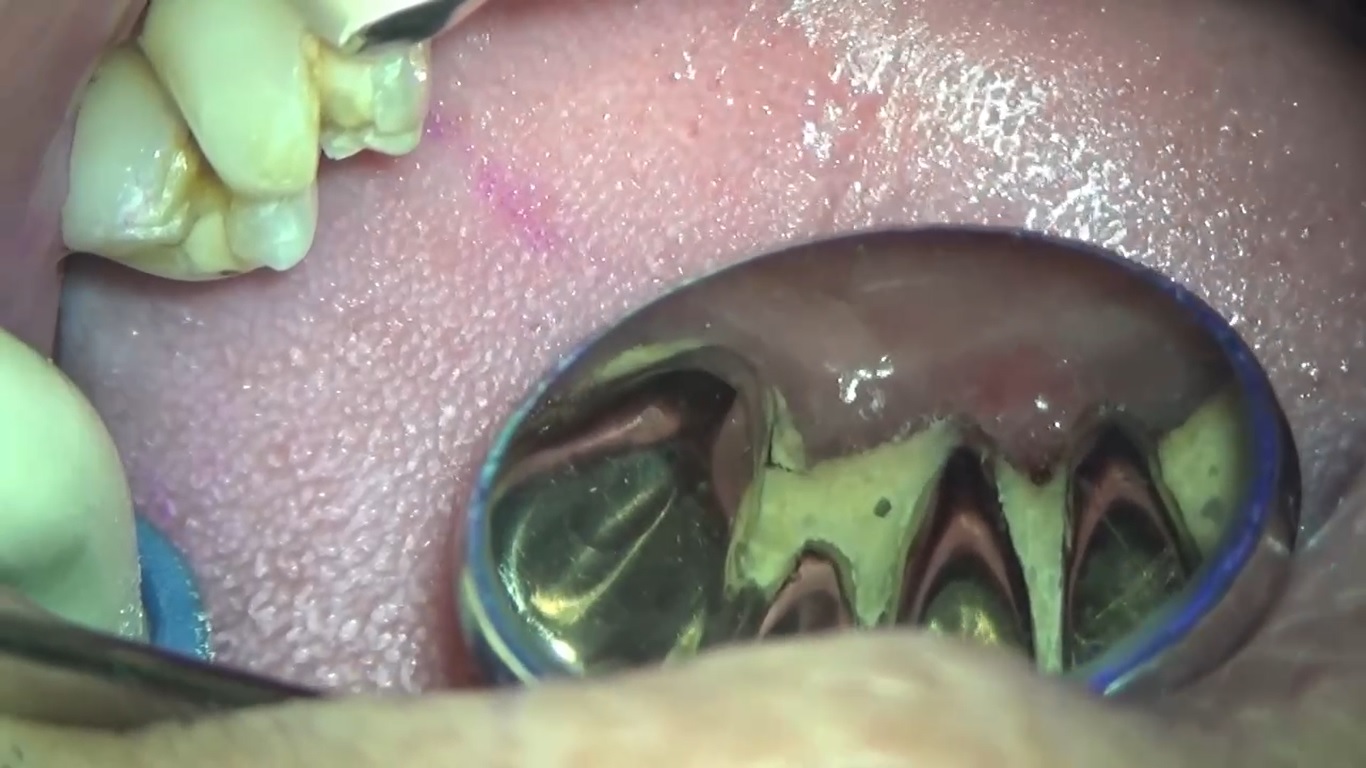

精度の高い被せ物を作る為には

こんにちは。 南館歯科クリニックの院長の木村です。 ぴったりとした被せ物を作る為には、しっかりと歯周病治療を行い、先ずは口腔内を健康な状態に回復させることがとても重要になります。 歯肉が…